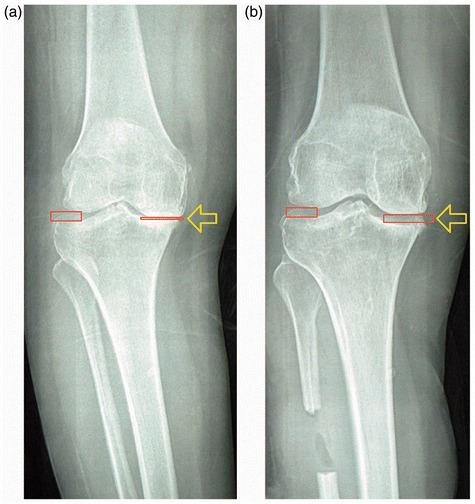

2. Proximal Fibular Osteotomy

Compared with knee replacement, PFO is a simpler surgical procedure, effectively relieves knee pain and also corrects the deformity for patients with medial compartment knee osteoarthritis (OA). PFO is performed by removing a 2 to 3 cm length of fibula bone at a site 6 to 10 cm below the knee. Full weight bearing and free mobilization are allowed after surgery. PFO relieves pain & corrects medial joint space by off-loading the weight bearing axis on the knee, thereby decompressing the medial compartment & loading the normal lateral compartment.

PFO is a simple, safe, fast and affordable surgery to relieve pain and improve joint function and the medial joint space in human knee osteoarthritis. PFO is a promising alternative in most developing countries because of their financial and healthcare delivery limitations. It may also constitute a promising alternative surgery for osteoarthritis of the medial compartment of the knee, especially for patients who cannot undergo TKA because of certain medical comorbidities. Furthermore, these patients can still undergo TKA in the future if it becomes necessary.